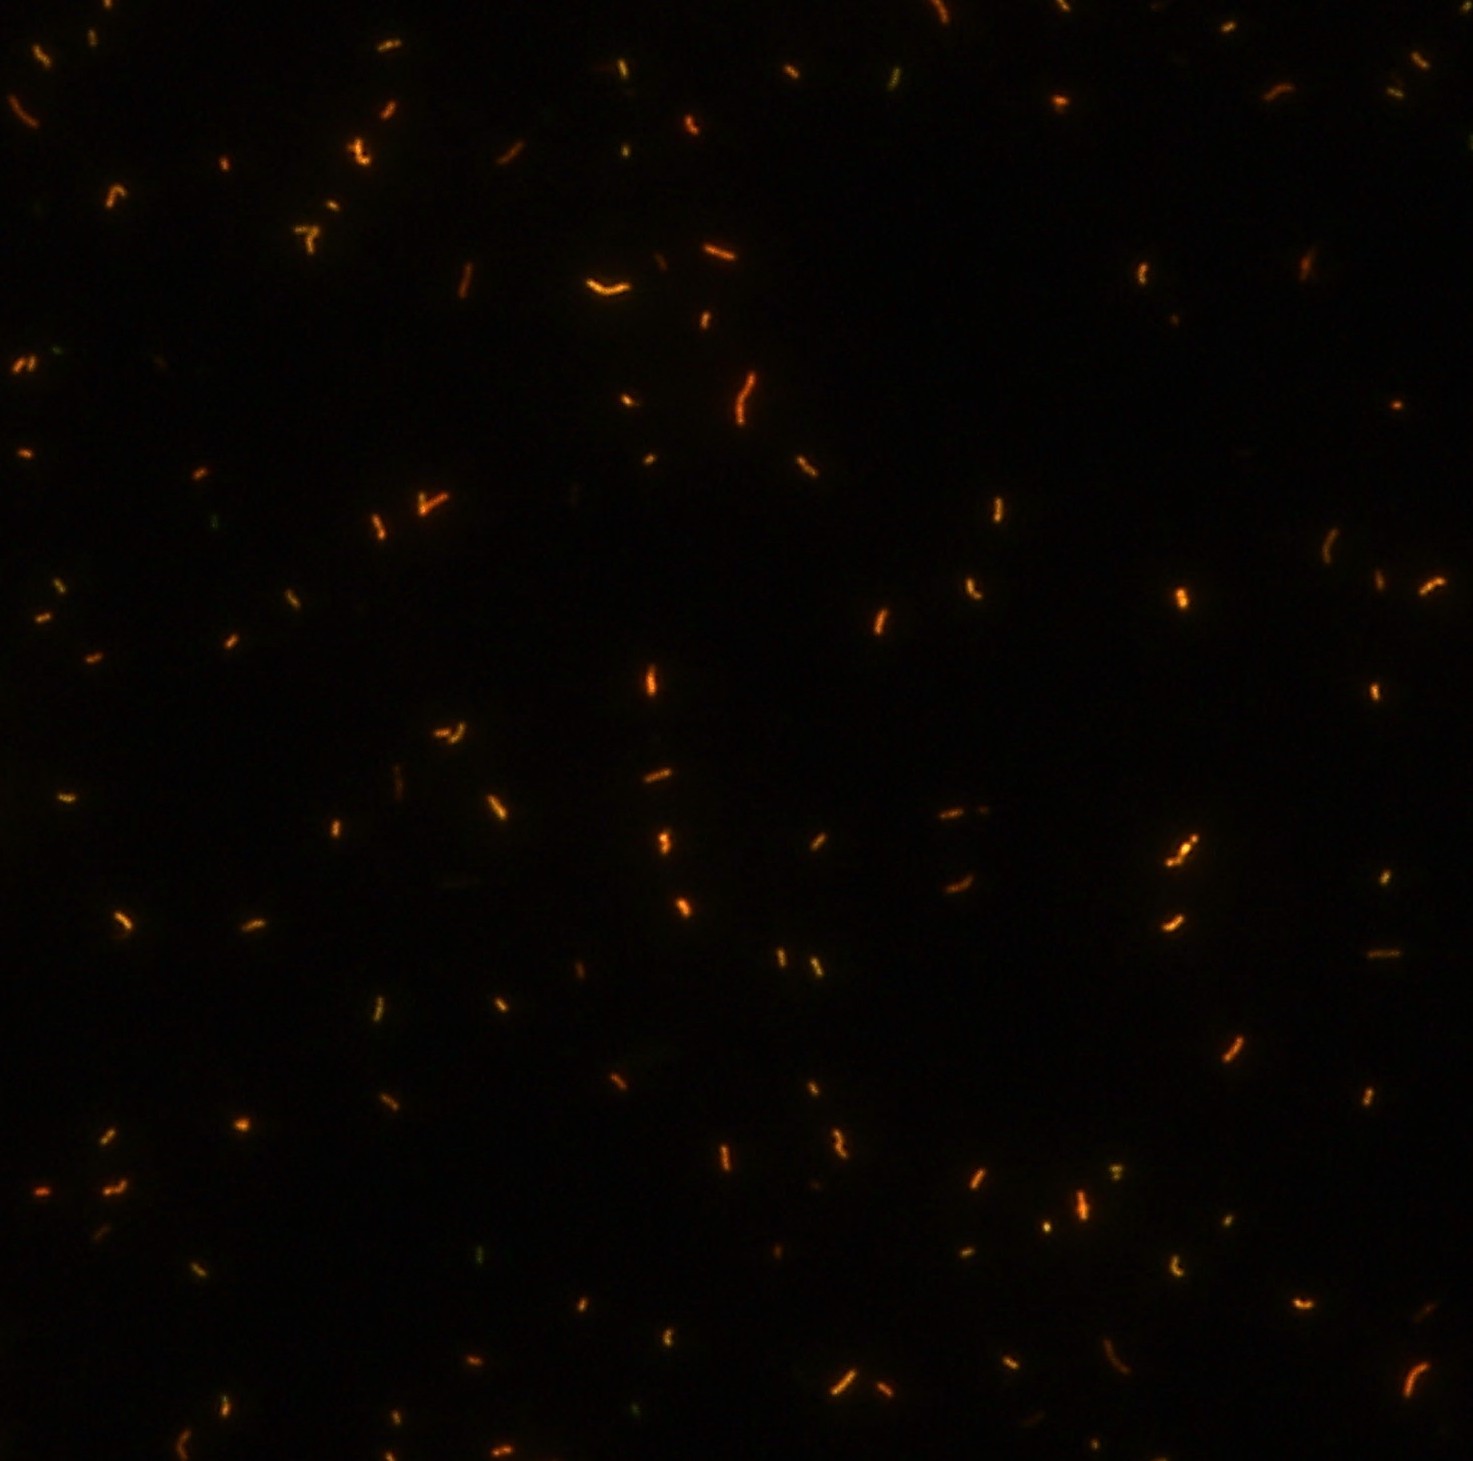

染色結(jié)果 (熒光法×400)

顯微染色技術(shù)是檢測(cè)結(jié)核桿菌方法之一。分枝桿菌細(xì)胞壁中含有分枝菌酸,其可以與染料牢固結(jié)合,具有“抗酸性”的特征。熒光染料金胺-羅丹明在染色中與抗酸生物細(xì)胞壁內(nèi)的分枝菌酸相結(jié)合,并耐受酸醇(脫色劑)清洗脫色。反染色劑高錳酸鉀被用來顯出染色生物。AFB(熒光)染色試劑盒設(shè)計(jì)既可用于自動(dòng)染色機(jī),也可用于手工染色。產(chǎn)品穩(wěn)定性好,染色效果佳。

用于分枝桿菌、諾卡菌等細(xì)菌抗酸染色,包括熒光染色。